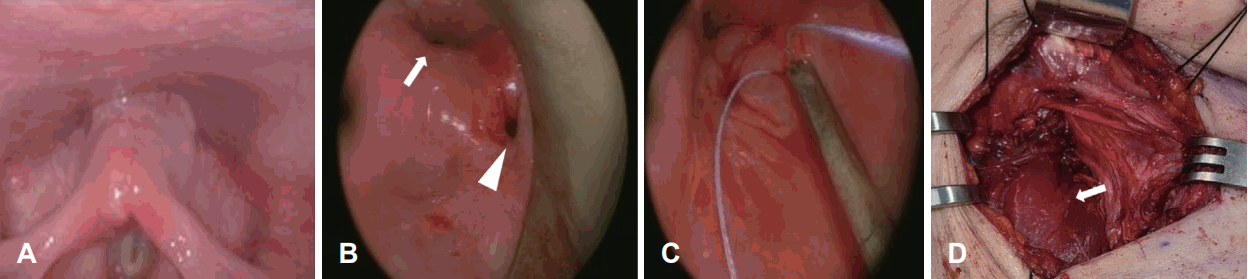

Esophagography findings. A: Contrast pooling in cervical esophagus and definite leakage immediately after esophagogastroduodenoscopy (EGD) (arrow). B: Minimal pooling of contrast in cervical esophagus and no definite leakage 1 month after EGD (arrow). C: No definite evidence of esophageal contrast leakage.

On esophagography, contrast leakage was found (Fig. 3A). Since the perforation of the hypopharynx was made iatrogenic and the patient preferred conservative management rather than external surgical approach, she was first treated with conservative treatment. Empirical antibiotics (ampicillin/sulbactam) combined with prohibition of oral intake was prescribed. One month after the event, the subcutaneous emphysema spontaneously resolved and minimal pooling of contrast in cervical esophagus without definite leakage was observed on esophagography (Fig. 3B). Two months after perforation, a small air pocket was seen but markedly decreased on neck CT (Fig. 2B). At that time, she was discharged in a condition where subcutaneous emphysema did not worsen, and oral intake was possible.

The patient progressed to a regular diet on the 7th day after surgery, based on the confirmation of no contrast leakage on esophagography and no abnormality on Neck CT (Fig. 3C and 2D). She had tolerable oral diet until last follow-up at 6 months after the last surgery.